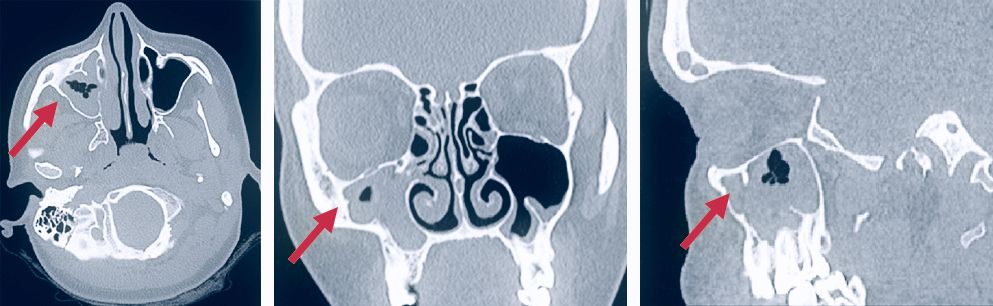

The arrows in the image indicate the pathological contents in the right maxillary sinus.

This is how the radiology department doctor sees your study. Based on the images obtained, he will be able to assess the anatomy of the paranasal sinuses and other organs of the area, diagnose the disease and help the clinician choose the optimal treatment regimen.